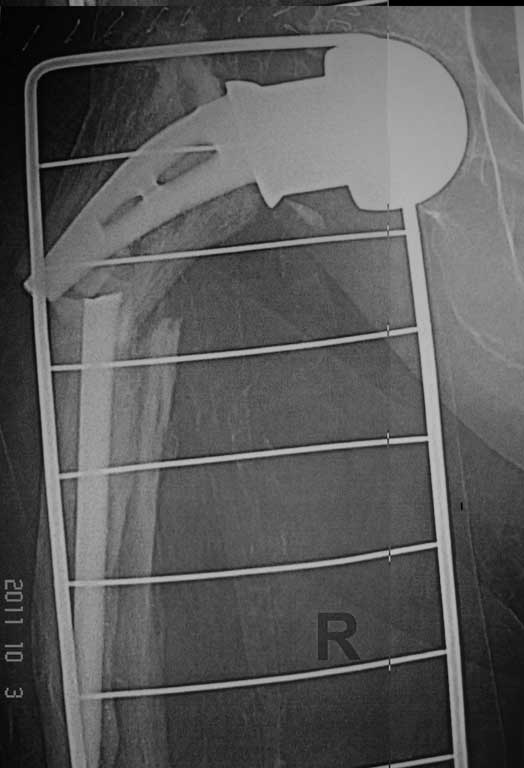

Перипротезный перелом

Добрый вечер. Уважаемые коллеги, впервые столкнулись с перипротезным переломом правой бедренной кости. Если есть опыт и идеи пожалуйста выскажите по поводу данного случая.

Женщина 86 лет, оперирована нами 6 лет назад по поводу перелома шейки правой бедренной кости . Травма двое суток назад - падение в квартире. Наши мысли по поводу данного случая - удаление протеза сломанной ножки и замена ревизионной цементной ножкой и модульной головкой , при этом не выполнять вскрытие кортикальной стенки в виде окна, для того чтобы убрать остатки цемента ,т.к эта процедура увеличит интраоперационную травму и кровопотерю, а с помощью рашпилей разработать канал, ввести в дистальный отломок цемент и посадить ножку,если будет нужно наложить серкляжные швы.